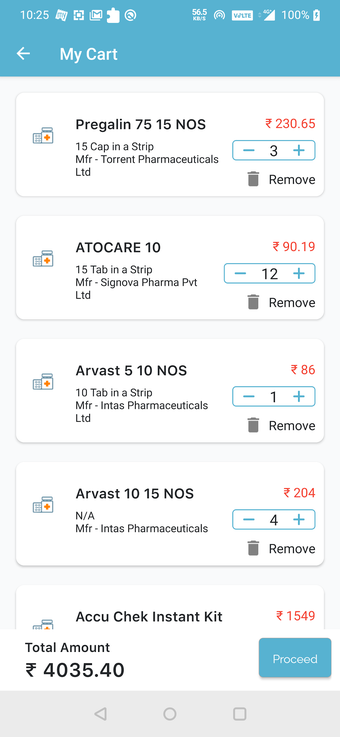

Możesz poprosić ich o wycenę kosztów leczenia lub recepty. Ponadto możesz skorzystać z usług apteki QuickObook. Jeśli pacjent nie ma ubezpieczenia zdrowotnego lub plan ubezpieczenia nie pokrywa kosztów leczenia, zostaniesz o tym poinformowany z góry.